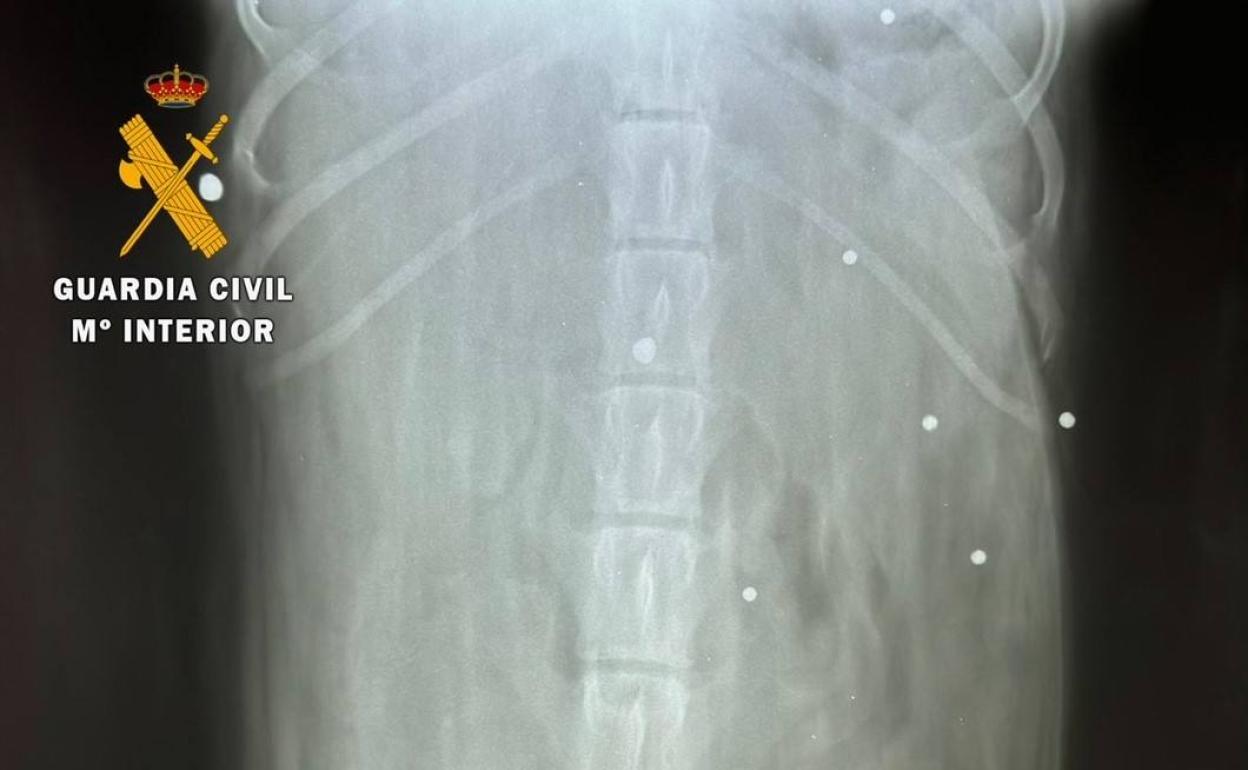

Agentes del Seprona de la Guardia Civil han investigado a un hombre de 66 años como supuesto autor de un delito de maltrato animal al ... disparar en tres ocasiones con su escopeta a un perro que entró en su finca provocándole 15 heridas por impacto de proyectil.

Los hechos tuvieron lugar el pasado día 21 de octubre, dentro del término municipal de Calzadilla (Cáceres), cuando la propietaria del animal se encontraba en una finca, y su perro se introdujo en la colindante, donde su vecino, un hombre de 66 años de edad, efectuó tres disparos de escopeta contra el animal provocándole heridas de diversa consideración.

Tras tener conocimiento de estos hechos, los agentes emprendieron las oportunas investigaciones que han culminado con la investigación del presunto autor material de los mismos, el cual, presuntamente y según informe veterinario, habría producido un total de 15 heridas por impacto de proyectil en el animal herido.